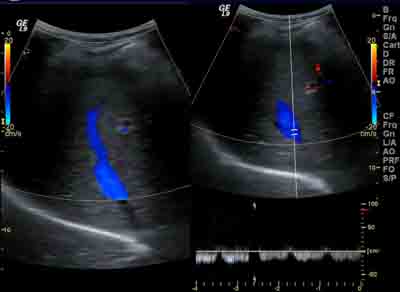

- l’aorte et les artères des membres inférieurs : explore une artériopathie oblitérante (artérite) un anévrysme de l’aorte, poplité, contrôle un geste chirurgical

- les artères et les veines de l'abdomen